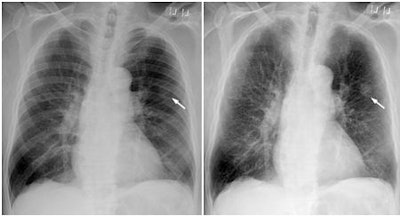

| Chest PA radiographs in 79-year-old man with nodular cancer in left upper lobe that was overlooked at the time of initial interpretation. Image at left is standard x-ray that shows cancer (arrow) partly overlapped with ribs. Bone suppression image at right shows the cancer but also enhances other structures, especially in the apical areas. Images courtesy of RSNA. |